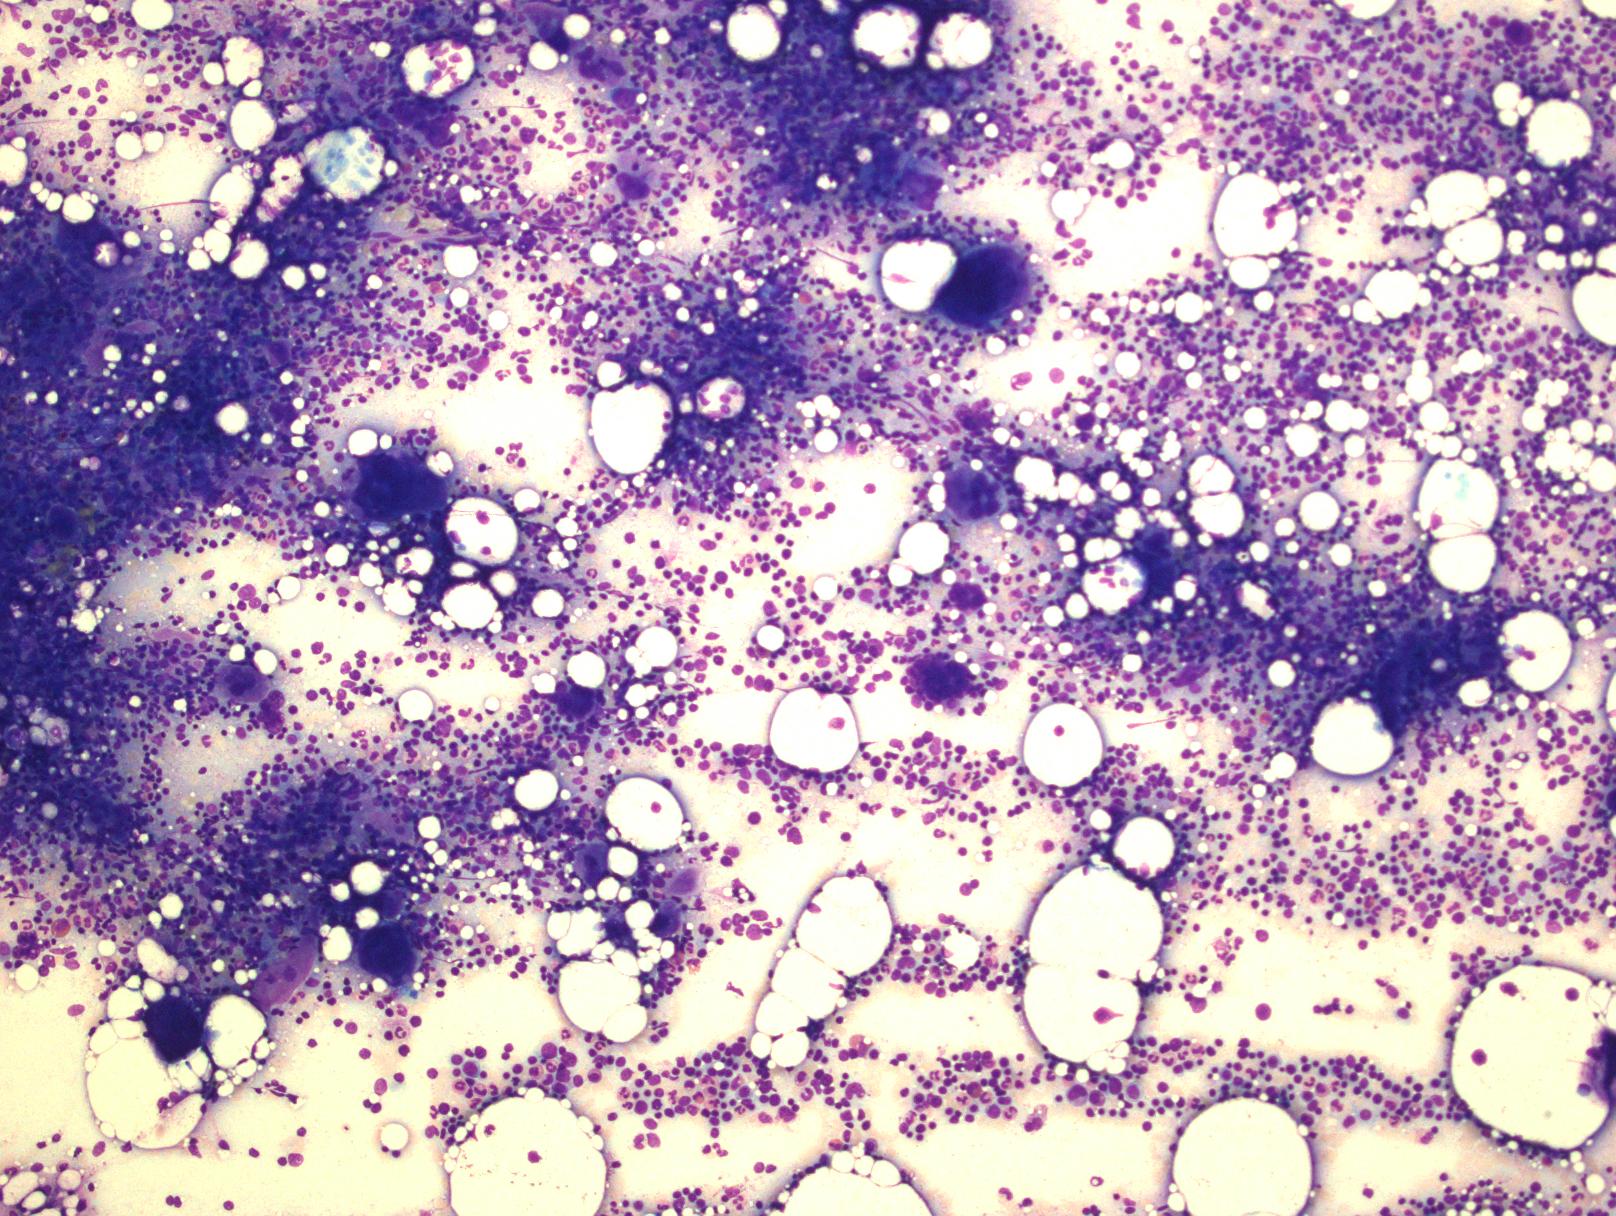

骨髓细胞密度正常,少数可表现为密度增加。最突出的表现是巨核细胞显著增生,以大巨核细胞为主,胞质丰富、成熟,核分叶深、分叶增多,骨髓中单个弥漫分布,也可疏松簇状分布。偶尔可见红系增生(常因出血引起增生性贫血所致),但粒系增生非常少见,如有也是轻度增生。无原始细胞增多,无髓系异型增生。网状纤维正常,仅 5%可有轻度增多,但从不超过 1 级,偶尔后续骨髓活检可见网状纤维化。初诊时明显的网状纤维或胶原化应排除 ET 的诊断。常见粒细胞伸入巨核细胞现象,但不具特异性。